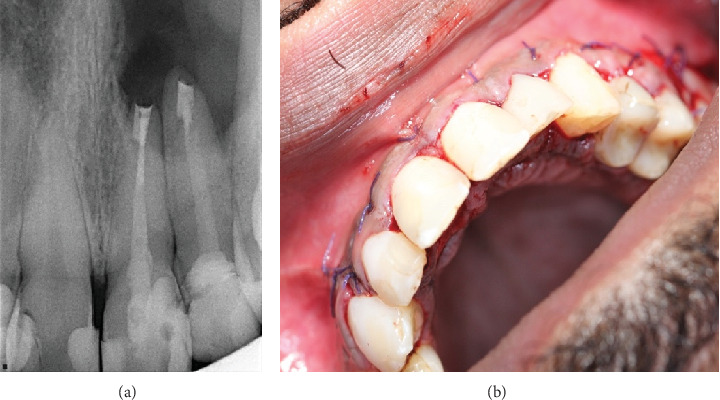

穿透性病变的致病过程导致两个皮质板的侵蚀和丧失。牙髓显微手术(MS)与骨移植物和膜放置(引导组织再生(GTR))是建议的治疗这种情况。这篇文章的目的是讨论一个不寻常的治疗方案,大的贯通病变不使用骨移植或膜。一名26岁的空军飞行员在高海拔地区旅行,因21号、22号和23号牙齿左上前病变引起的疼痛和肿胀到牙髓科就诊。经过彻底的临床检查、病史、临床和放射学检查,诊断出与先前治疗过的牙齿有关的全面病变。由于其工作性质,治疗方案包括不使用GTR的牙髓质MS。在3年多的时间里,常规随访对追踪受损区域的愈合过程至关重要,最终导致完全恢复。该病例强调了获得全面的病史和使用多学科方法诊断和处理全面病变的重要性,并取得积极的结果。

The pathogenic process of through-and-through lesions leads to erosion and loss of both cortical plates. Endodontic microsurgery (MS)with bone graft and membrane placement (guided tissue regeneration (GTR)) is the proposed treatment for such cases. This article is aimed at discussing an unusual treatment protocol for a large through-and-through lesion without the use of bone grafting or membrane. A 26-year-old Air Force pilot traveling at high altitudes presented to the Endodontic division for management of pain and swelling related to the upper left anterior lesion concerning Teeth #21, #22, and #23. Following a thorough clinical examination, medical history, and clinical and radiographic examination, the diagnosis of the presence of a through-and-through lesion related to previously treated teeth. The treatment plan included endodontic MS without the use of GTR due to his work nature. Over 3 years, routine follow-ups were essential for tracking the damaged area's healing process, which ultimately resulted in full recovery. This case emphasizes how crucial it is to obtain a thorough history and use a multidisciplinary approach to diagnose and manage through-and-through lesions, achieving positive outcomes.